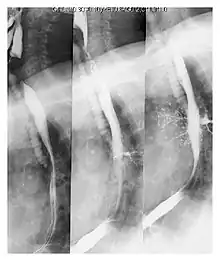

Upper gastrointestinal series at the level of the esophagus, showing pulmonary aspiration of the radiocontrast agent